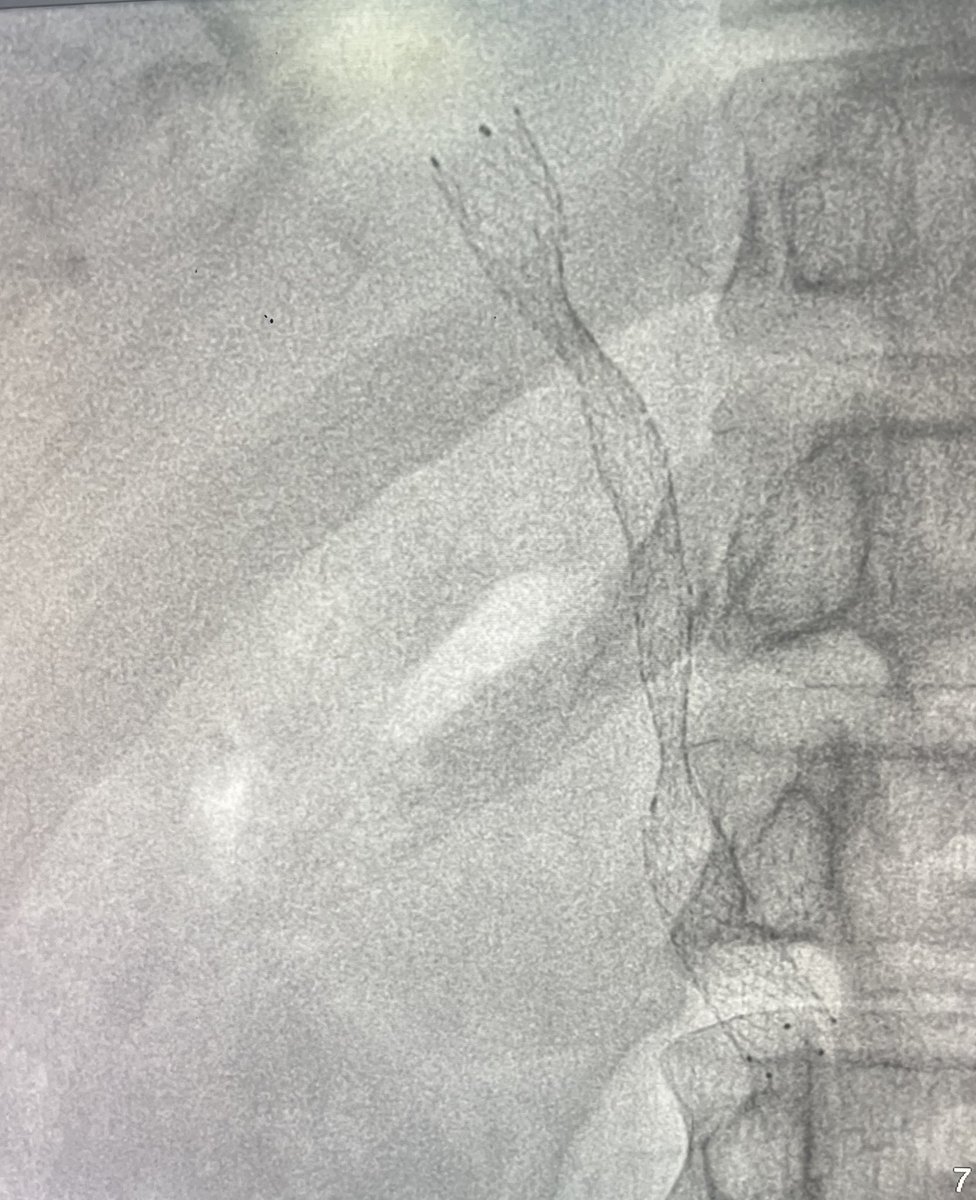

Case 143: with @BhaveshPopat7 @DrAntariksh @Rishi0591 @DrVaibhavThakur Rohan L . CLI; post debridement; non healing wound; PTA-CTO with reformation at plantar arch; luminal-subintimal antegrade crossing with micro balloon-Fielder combo; PTA + plantar loop arch plasty 2.5 mm; images 👇 . #irad #meded #medx #medtwitter #cardiotwitter #radiology #virad #clifighters #pvd @SIRspecialists @SIR_ECS @SIRRFS @cirsesociety @ETF_IRtrainees @_backtable @CLIfighters